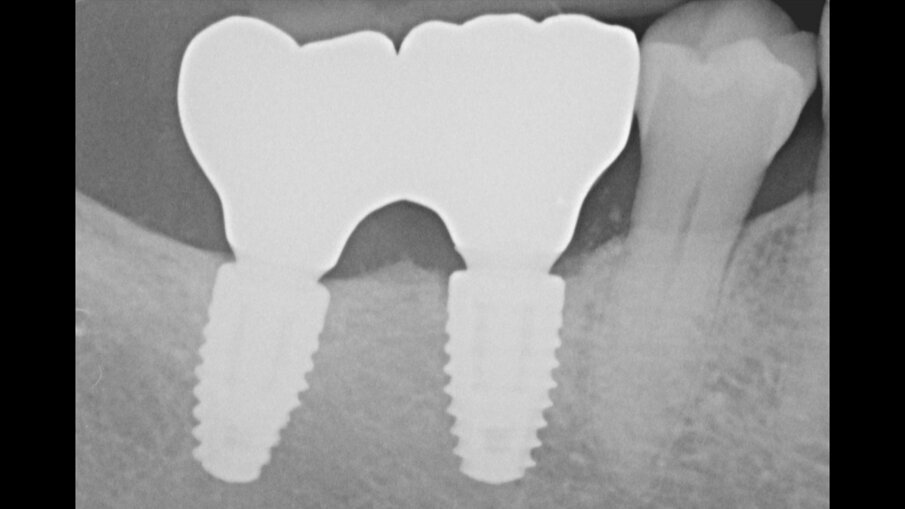

Figg. 12a, 12b_Immagine clinica e radiografica che mostrano il manufatto protesico provvisorio.